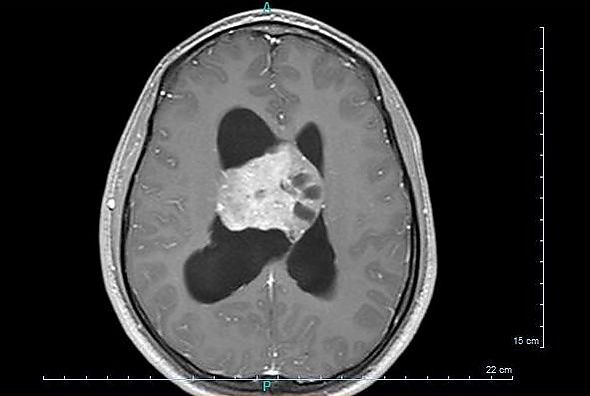

Центральная нейроцитома

Центральные нейроцитомы обычно располагаются супратенториально в боковом желудочке(боковых желудочках) и/или третьем желудочке. Наиболее частым местом является передняя часть одного из боковых желудочков с последующим распространением в другой боковой и третий желудочки. Вовлечение прозрачной перегородки вероятно является особенностью опухоли.[9] Изолированное поражение третьего и четвертого желудочков встречается редко.[10]

Макроскопически центральная нейроцитома имеет сероватый цвет, напоминающий серое вещество с участками кровоизлияния. Опухоль мягкой консистенции, овоидной формы, дольчатого или узловатых строения, которые обычно четко очерчены. На разрезе можно отметить некоторую шероховатость, которую связывают с кальцификацией.